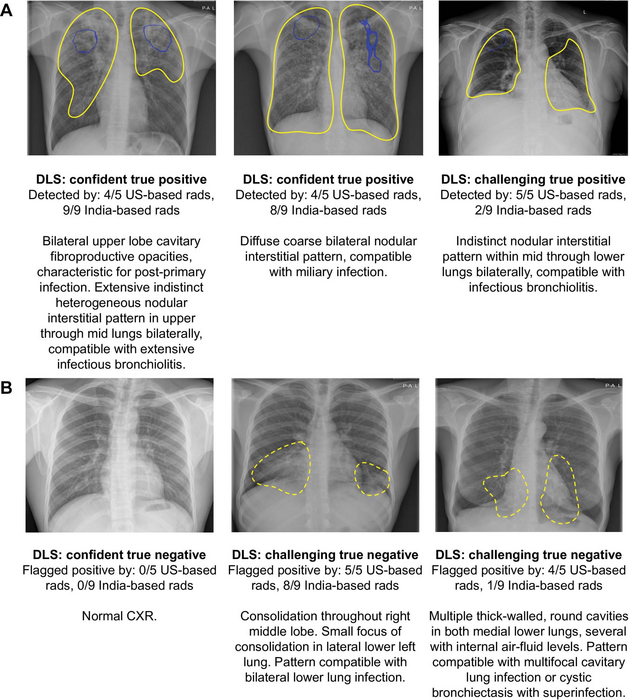

Kazemzadeh and colleagues developed and assessed an AI system that can quickly and automatically evaluate chest X-rays for TB. The system uses deep learning, a type of AI that can be applied to teach the computer to recognize and predict medical conditions. The researchers developed the system using data from nine countries. They then tested it on data from five countries, covering multiple high-TB-burden countries, various clinical settings and a wide range of races and ethnicities. Over 165,000 images from more than 22,000 patients were used for model development and testing.

Analysis with 14 international radiologists showed that the deep-learning method was comparable to radiologists for the determination of active TB on chest X-rays.